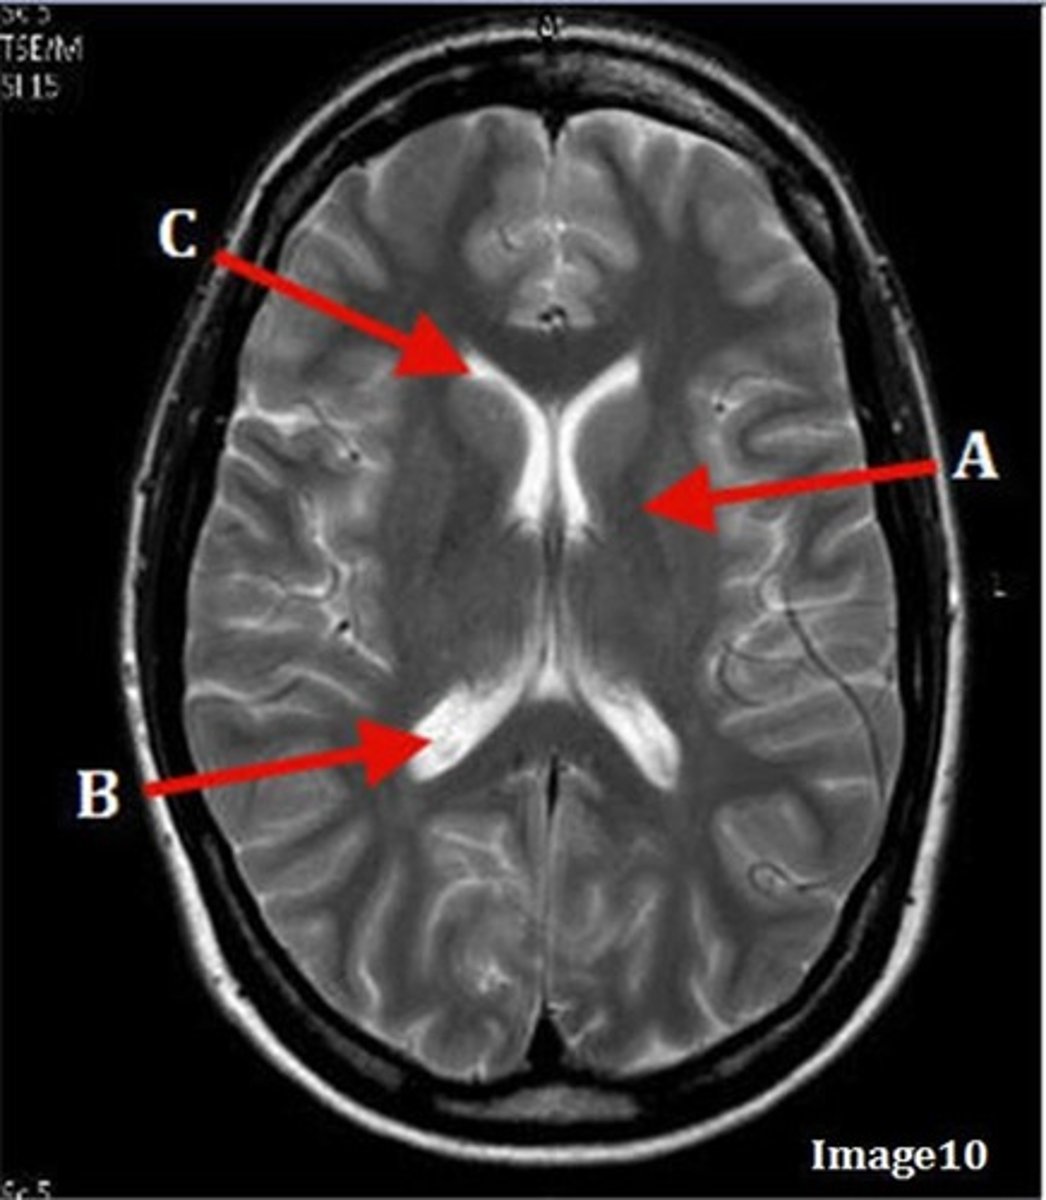

A

lateral ventricle

B

corpus callosum

C

thalamus

caudate nucleus

third ventricle

A (region)

dark band is called?

basal ganglia region

internal capsule

posterior horn of lateral ventricle

anterior horn of lateral ventricle

F

lentiform nucleus

E

gray matter

corpus

fornix

internal carotid artery